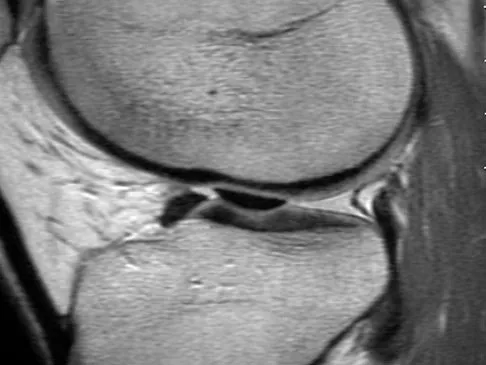

Figures 20a and 20b show the sagittal and coronal T1-weighted MRI scans of a patient's left knee. Abnormal findings include

Explanation